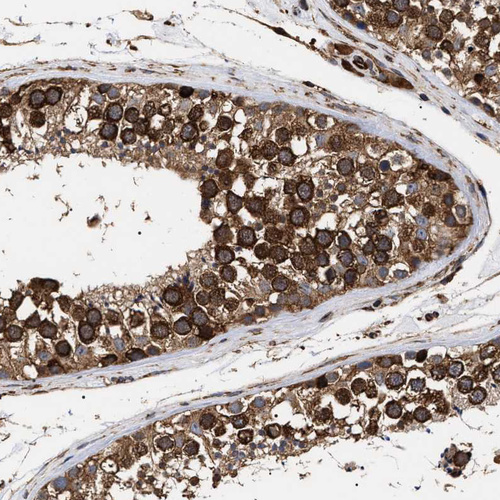

Immunohistochemical staining of human testis shows strong cytoplasmic positivity in cells in seminiferous ducts.